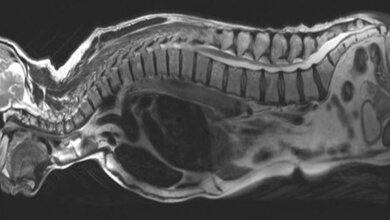

Die Spezialsprechstunde wurde in das Einzelzentrum für seltene Bluterkrankungen des Zentrums für Seltene Erkrankungen am Universitätsklinikum Heidelberg integriert. Dort wurden jährlich bisher etwa 100 Kinder und Jugendliche mit angeborenen Anämien von dem interdisziplinären Team betreut. Bei den angeborenen Anämien liegt häufig ein Defekt oder Mangel des roten Blutfarbstoffs Hämoglobin zugrunde, dessen zentraler Bestandteil Eisen ist. Die häufigsten dieser Erbkrankheiten weltweit sind die Sichelzellkrankheit und die Thalassämie.

Auch Störungen des Eisenstoffwechsels können Anämien zur Folge haben. Die genetischen Ursachen dieser Krankheit sind größtenteils unbekannt, vielfältig und schwer zu diagnostizieren. Der zugrundeliegende Defekt kann häufig nicht aufgeklärt werden, wodurch eine angemessene Behandlung erschwert wird. Die bislang einzige Therapie ist die Stammzelltransplantation. Zur Heilung erhalten die Betroffenen hier blutbildende Zellen eines fremden Spenders, die fortan funktionsfähiges Hämoglobin herstellen.